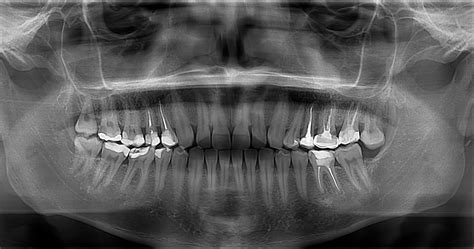

Quiste dental visible en una radiografía.

En las primeras etapas pueden ser asintomáticos, pero a medida que crecen, pueden causar dolor, inflamación y otros síntomas. El diagnóstico generalmente se realiza mediante una combinación de exámenes clínicos, radiografías y otras pruebas de diagnóstico.